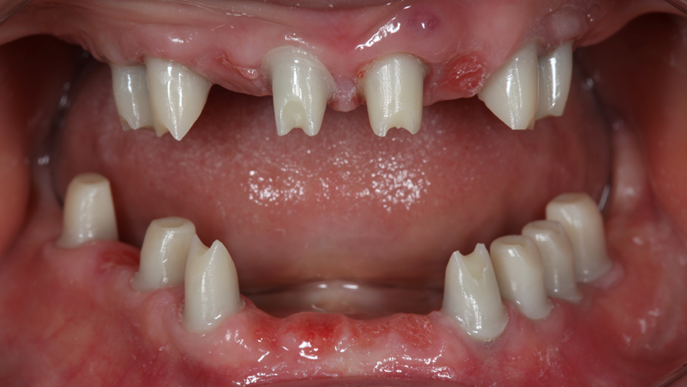

- Courtesy of Dr. Jong Cheol Kim, Korea